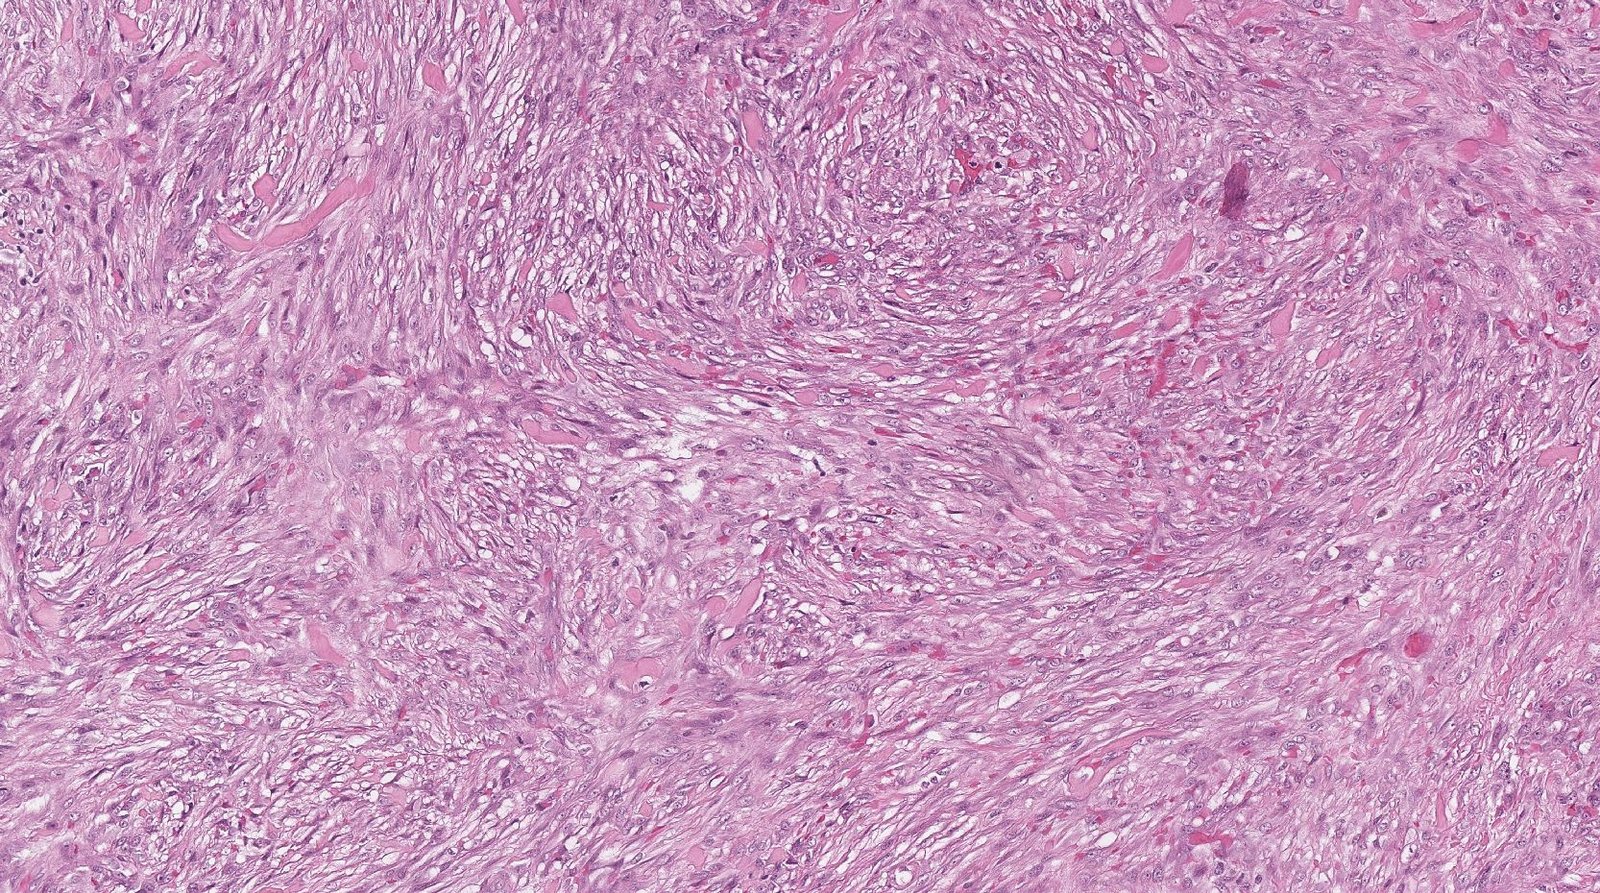

Case: WristMass

Specials to Order:

Final Diagnosis: